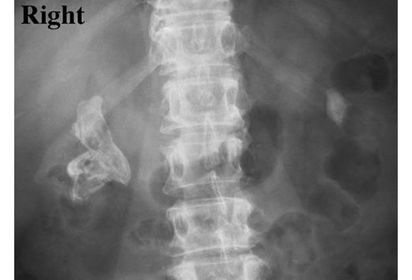

Pyelonephritis (Right) Inflammation of the kidney and renal pelvis Acute: escherichia coli invades the renal tissue, commonly enters the kidney through retrograde from the bladder of through blood Chronic: chronic reflux occurs of infected urine from the bladder into the renal pelvis More common in females symptoms: flank pain, bacteriuria, pyuria, dysuria, nocturia, and increased frequency of urination Acute: calyces are enlarged, blunting of calyces Chronic: decreased kidney size with destruction and scarring due to fibrosis